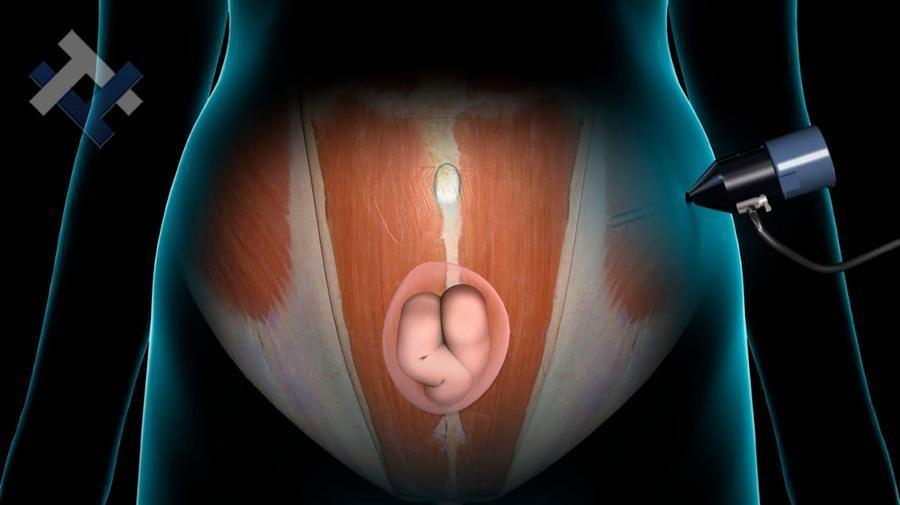

Ο Γενικός Χειρουργός Λιάγκος Γεώργιος MD PhD εκτελεί τις επεμβάσεις Λαπαροσκοπικά, Ενδοσκοπικά, Ανοιχτά Ελάχιστα Επεμβατικά και με Laser. Η θεραπεία εξατομικεύεται σε κάθε ασθενή ανάλογα με τις ανάγκες του. Αναλαμβάνει περιπτώσεις όπως κήλες και κοιλιοκήλες (αντιμετώπιση βουβωνοκήλης, αντιμετώπιση ομφαλοκήλης, θεραπεία επιγαστρικής κήλης, κήλη των αθλητών (Σύνδρομο κοιλιακών προσαγωγών), αντιμετώπιση μετεγχειρητικής κήλης, θεραπεία Μηροκήλης), πέτρες στη χοληδόχο κύστη, λαπαροσκοπική χολοκυστεκτομή, αντιμετώπιση Κύστη Κόκκυγος με λέιζερ (laser), παθήσεις πρωκτού, χειρουργική laser σύγχρονων κυκλικών ινών (αιμορροΐδες αντιμετώπιση, θεραπεία αιμορροϊδων με laser (LHP), αφαίρεση αιμορροΐδων με υπερήχους (HALL-RAR), χωρίς Χειρουργείο με ελαστικούς δακτυλίους (Τεχνική BARON-RBL), θεραπεία ραγάδας πρωκτού (Ραγάδα δακτυλίου), θεραπεία περιεδρικού συριγγίου, θεραπεία περιεδρικού αποστήματος, κονδυλώματα πρωκτού Θεραπεία, δερματικό ράκος (Skin tag) εκτομή, αντιμετώπιση Kνησμού, καρκίνος πρωκτού θεραπεία), παθήσεις Δέρματος, χειρουργική με laser CO2, αφαίρεση μορφωμάτων δέρματος - βιοψίες, αφαίρεση ελιάς (Σπίλου), σμηγματογόνος κύστης θεραπεία, αφαίρεση λιπώματος, είσφρυση όνυχος χειρουργείο, καρκίνος δέρματος θεραπεία, οξεία σκωληκοειδίτιδα, παθήσεις Λεπτού και Παχέος Εντέρου, ειλεός λεπτού εντέρου, εκκολπωμάτωση (Εκκολπωματίτιδα) σιγμοειδούς, καρκίνος παχέος εντέου, κολοστομίες, port χημειοθεραπείας κ.α. εξυπηρετώντας Παγκράτι και γύρω περιοχές.